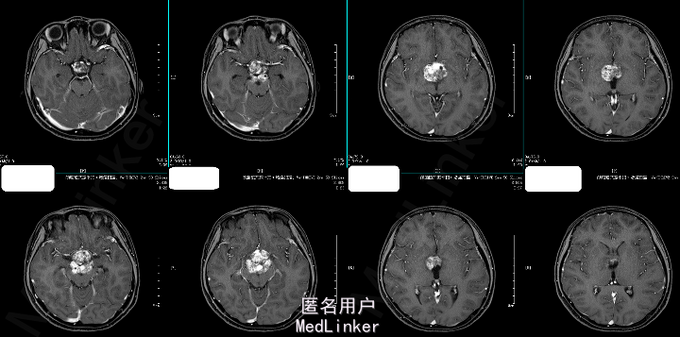

诊断:鞍上区恶性肿瘤:颅内生殖细胞肿瘤 处理:放疗。(3D-CRT 36GY/FX),胸腺肽增强免疫力及副作用对症处理。 (2015-06-24复查头颅MR结果如下)